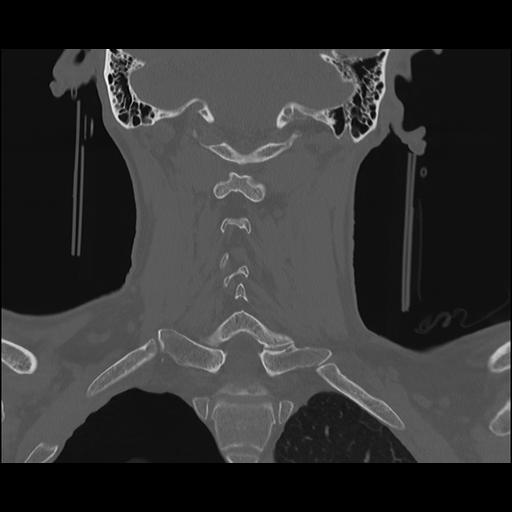

16 HUESO,,Coronal,2.000,HUESO,Coronal,